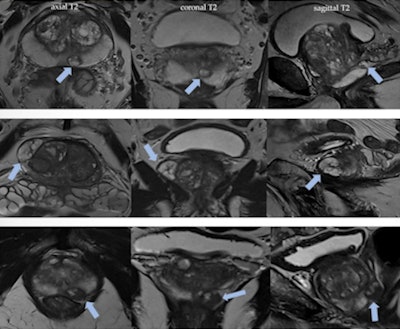

Acute and chronic prostatitis can cause signal changes in both the peripheral and transition zones that are indistinguishable from prostate cancer, and they should be evaluated by applying the PI-RADS v2.1 system, assigning the corresponding category, the authors wrote.

An evolved acute prostatitis may present with intraglandular abscess formation as a complication with the following MRI characteristics: hyperintense on T2-weighted imaging, ring enhancement, restricted DWI, and diffusion on ADC.

In cases of granulomatous prostatitis, uncommon chronic inflammation is usually detected by histopathological analysis of a biopsy, since the MRI appearance can be identical to a suspicious PI-RADS 4/5 lesion. Idiopathic etiology exists in about 60% of patients and may be associated with previous treatment of bladder cancer with Bacillus Calmette-Guerin, a type of immunotherapy drug.